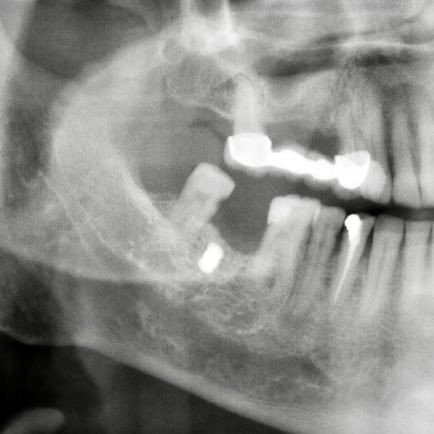

Erzincan'da yaşayan 63 yaşındaki Faik Akın, 15 yıl önce benzinli testereyle odun keserken testerenin zincirinin kopması sonucunda etrafa saçılan parçaların yüzüne isabet etmesi ile yaralandı. Hastaneye müracaat etmeyen Faik Akın'ın yüzüne gelen demir parçalardan biri damağında yıllarca kaldı. Diş tedavisi için hastaneye gelen Faik Akın'ı muayene eden Ağız ve Çene Cerrahı Dr. Öğretim Üyesi Yakup Gülnahar, hastanın röntgen filmine bakınca damağında bir nesne olduğunu belirledi. Hastanın ameliyatını gerçekleştiren Dr. Yakup Gülnahar, 1 saatlik operasyonla damağa saplanan demiri çıkardı.

Ameliyatı gerçekleştiren Dr. Yakup Gülnahar, "Hastanın muayenesinde rutin röntgen filmi istedik. Röntgenlerde hastanın yanağında bir cisim olduğunu anladım. Kendisine daha önce implant yaptırıp yaptırmadığını sordum. Kendisi implant yaptırmadığını söyledi. Bu sefer hastanın yanağında ne olabilir diye düşünürken hastanın 15 yıl önce benzinli odun testeresi ile çalışırken testerenin zincirinin koptuğunu ve etrafa saçılan parçalardan yanağına isabet ettiğini öğrendik. Hastamızı ameliyata aldık ve yanağındaki demir parçayı çıkardık. Hastamız da şu an gayet iyi bir durumda" şeklinde konuştu.